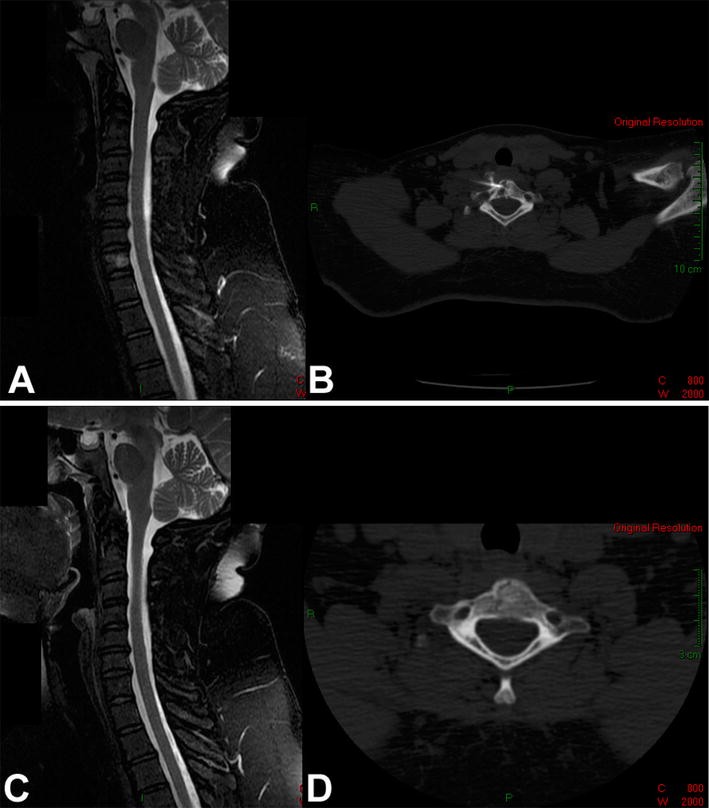

a Sagittal T2-weighted MRI with fat suppression of the cervical spine of a 43-year-old woman with a painful osteolytic lesion of the C7 vertebral body. b CT-guided frozen section biopsy showed eosinophilic granuloma; intralesional methylprednisolone injection was performed. c Sagittal T2-weighted MRI with fat suppression. d Axial CT scan show complete reconstitution of the lesion 4 years after diagnosis and treatment